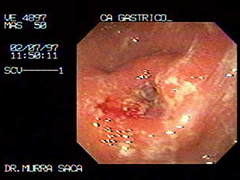

Cáncer Gástrico:

Se observa un tumor en forma de dona ulcerada que ha obstruido el antro.